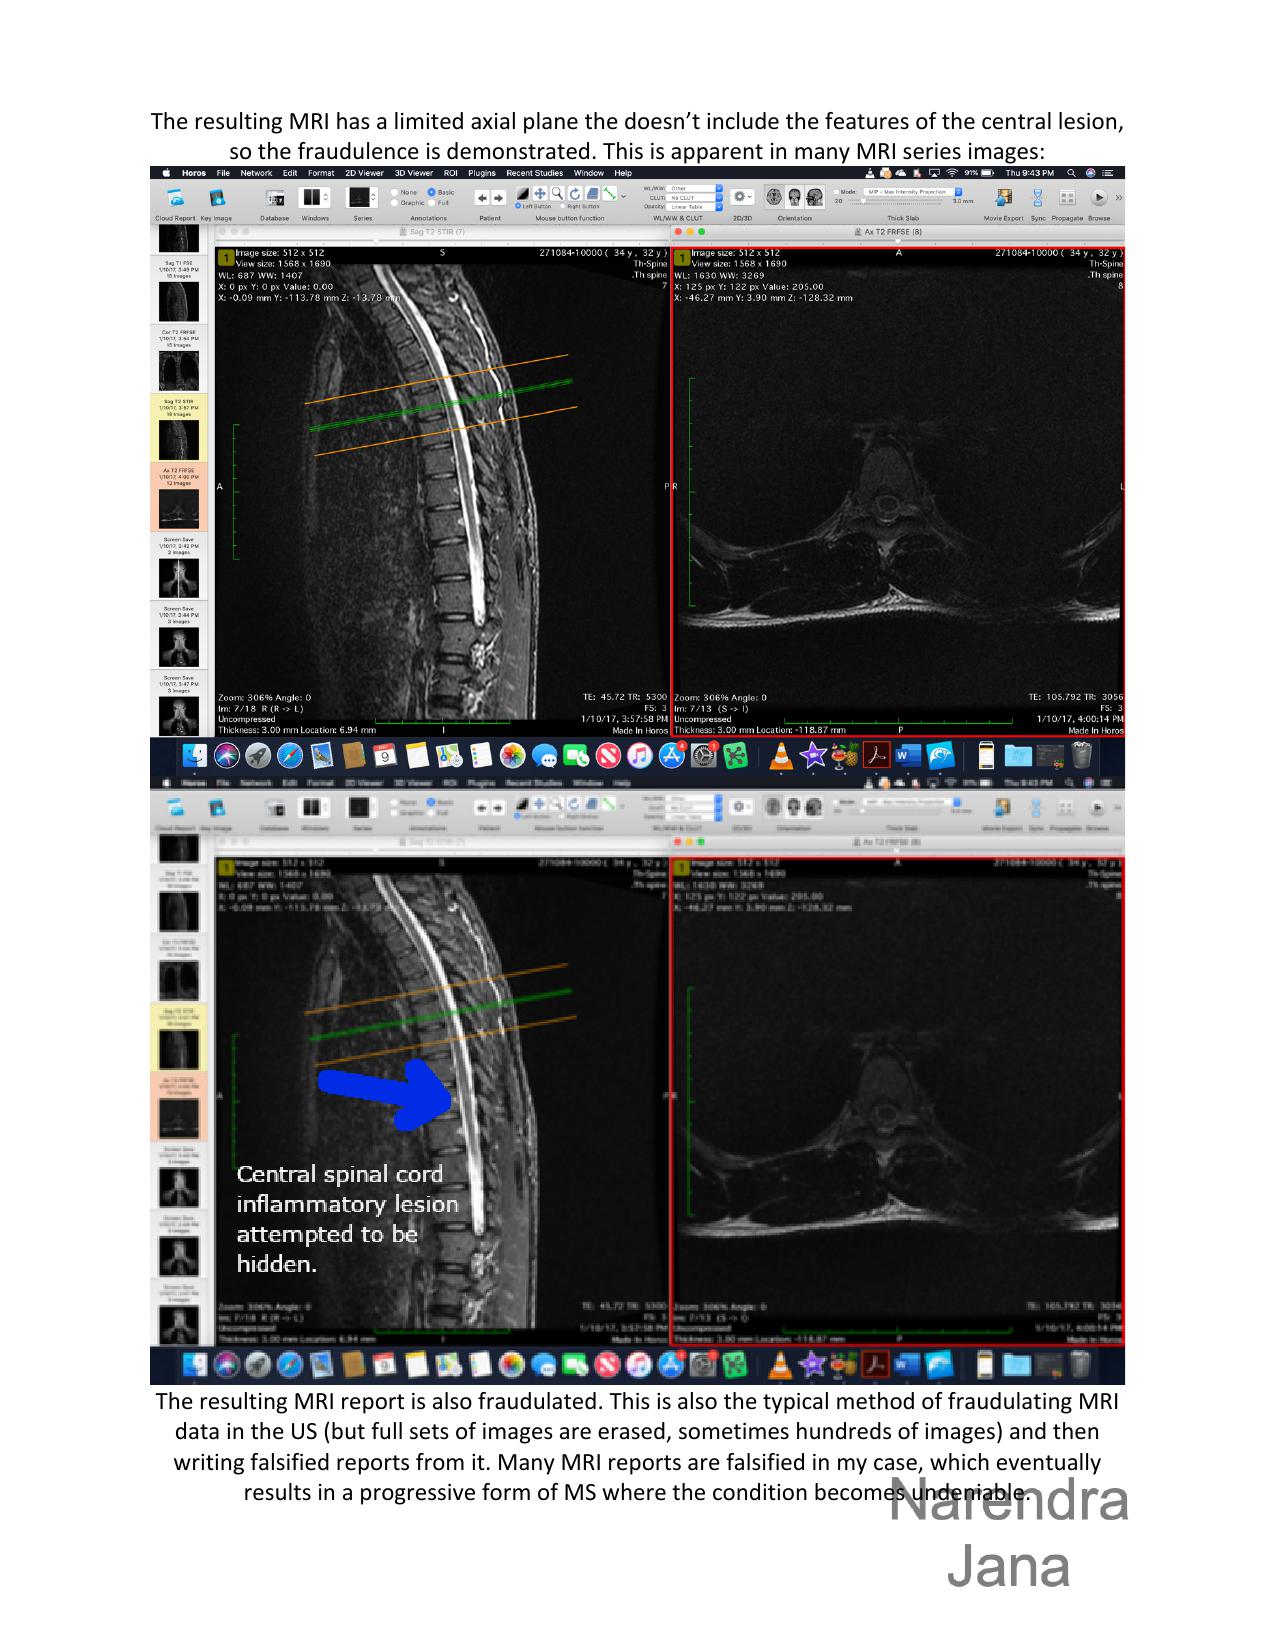

The falsification in Dr. Pia Schumacher's statement can be determined by the evidence of fraud in another setting (the fraud takes place on January 10th 2017 in Riga, Latvia in Riga 1st Hospital). This is the presentation of fraud in another setting and it pertains to how a radiologist tries to hide medical data by erasing sections of a MRI that shows a disease pathology.

2.     2. There are central lesions in the MRI series which the radiologist identifies and hides. By hiding it the radiologist revels the location of the central lesions and the intent of both the radiologist and the Dr. Pia Schumacher. These are demyelination lesions typical of MS (which Dr. Pia mentions). The MRIs looked at by Dr. Pia have gross central lesions but were attempted to be hidden by former radiologists.